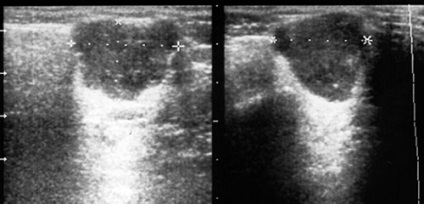

Ultrahang vizsgálat jelentősen hozzájárul a diagnózis nagy nyálmirigyek bolevany.

A gyulladásos betegségek, a mirigyeket echography lehetővé teszi a differenciál diagnosztikájában különböző formáinak mumpsz, azonosítani angiosialitis - gyulladás a csövekben a nyálmirigyek, a gyulladás felismerik vnutrizhelezistyh nyirokcsomók (nyirokcsomó), és hogy tisztázza a szakaszban. Mindez lényegében egy differenciálódását sebészeti és nem sebészeti patológiai a mirigyeket (ábra. 1-7).

Ábra. 1. jobb oldali akut mumpsz.